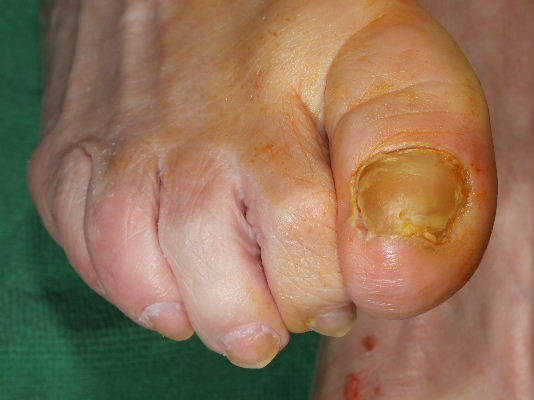

Onicomicosis. Hiperqueratosis